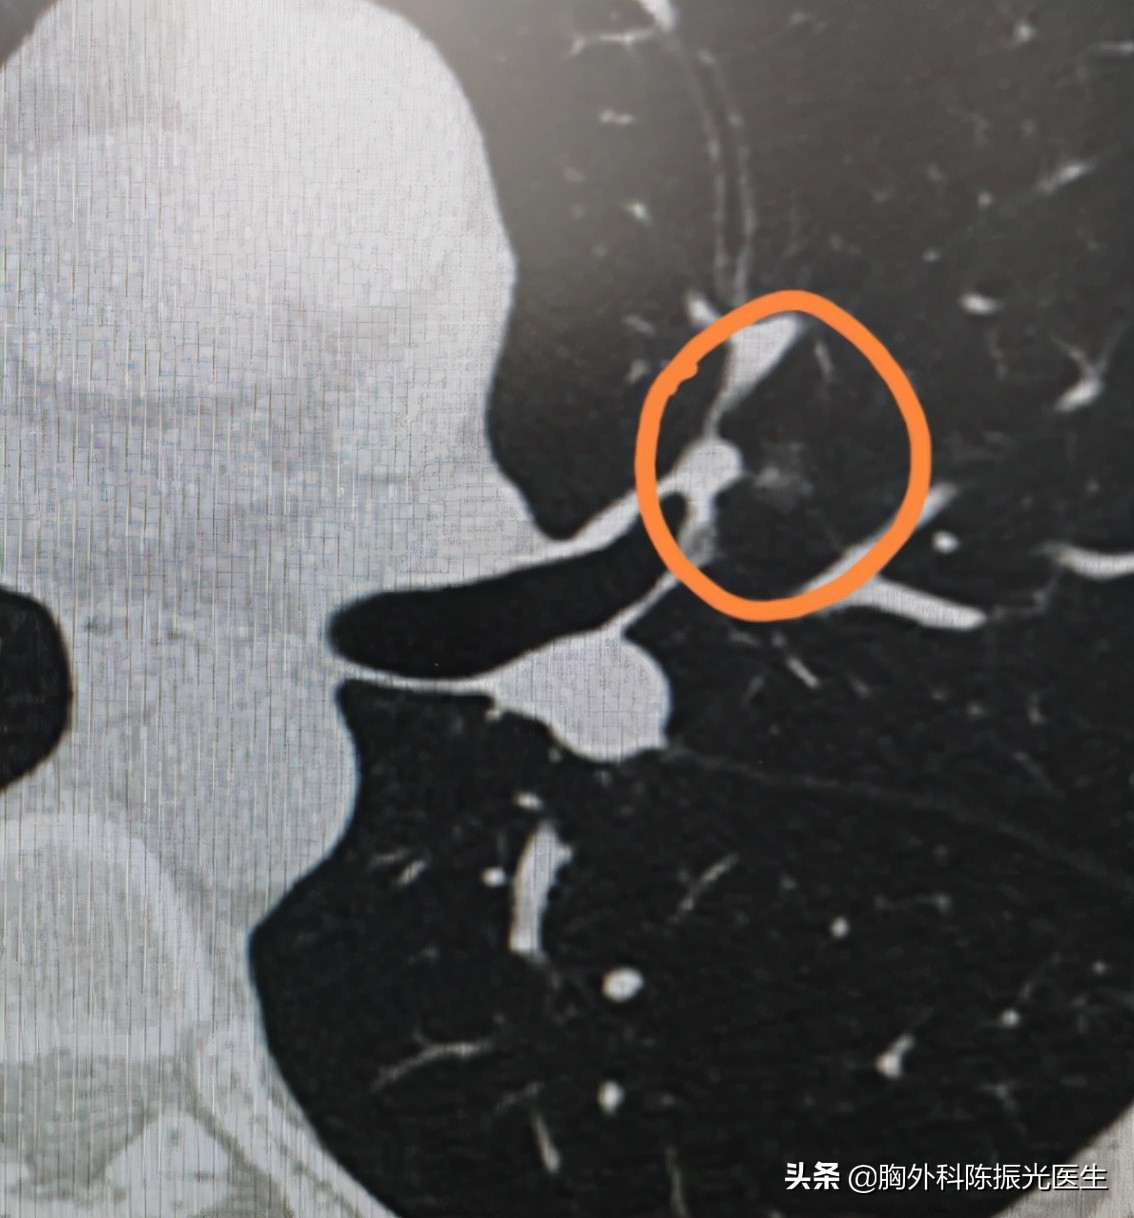

“我最近体检胸部CT平扫检查,发现左肺上叶前段与上舌段交界处、右肺下叶背段这两个地方,各发现一个磨玻璃密度结节影,大小分别是8毫米x 6毫米、8毫米x 5毫米,同时右肺下叶背段发现一个实性小结节,直径4毫米,同时检查血肿瘤标志物NSE稍稍高了一点,是不是长了肺癌?”

“您的这两个结节,虽然已经达到8毫米,但是性质上来说还需要进一步观察,尤其是动态观察结节大小形态的变化走势,目前并不能诊断肺癌。”